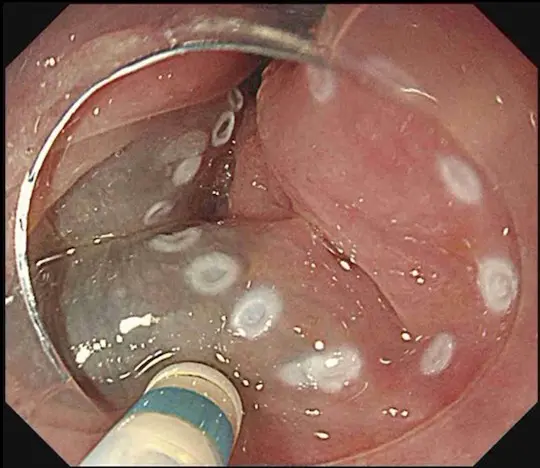

黄色い矢印で示す部分が少し赤くなっています。この部分が咽頭癌です。非常に分かりにくい病変です。

ヨードと呼ばれる薬液で染色すると、白い矢印で示す部分に咽頭癌(周りと色の違う部分)が浮かび上がってきます。

咽頭癌を取り囲むように、電気メスで白いマークを付けました。治療の際の目印になります。